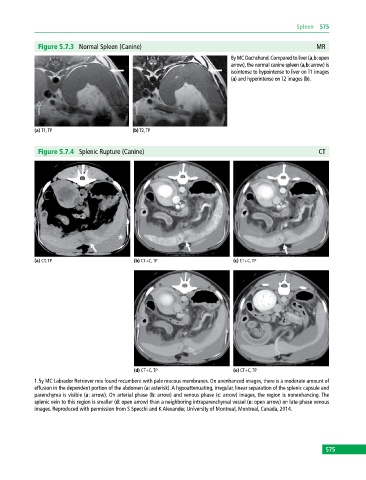

Figure 5.7.3 Normal Spleen (Canine) MR

8y MC Dachshund. Compared to liver (a,b: open

arrow), the normal canine spleen (a,b: arrow) is

isointense to hypointense to liver on T1 images

(a) and hyperintense on T2 images (b).

(a) T1, TP (b) T2, TP

Figure 5.7.4 Splenic Rupture (Canine) CT

(a) CT, TP (b) CT+C, TP (c) CT+C, TP

(d) CT+C, TP (e) CT+C, TP

1.5y MC Labrador Retriever mix found recumbent with pale mucous membranes. On unenhanced images, there is a moderate amount of

effusion in the dependent portion of the abdomen (a: asterisk). A hypoattenuating, irregular, linear separation of the splenic capsule and

parenchyma is visible (a: arrow). On arterial phase (b: arrow) and venous phase (c: arrow) images, the region is nonenhancing. The

splenic vein to this region is smaller (d: open arrow) than a neighboring intraparenchymal vessel (e: open arrow) on late‐phase venous

images. Reproduced with permission from S Specchi and K Alexander, University of Montreal, Montreal, Canada, 2014.